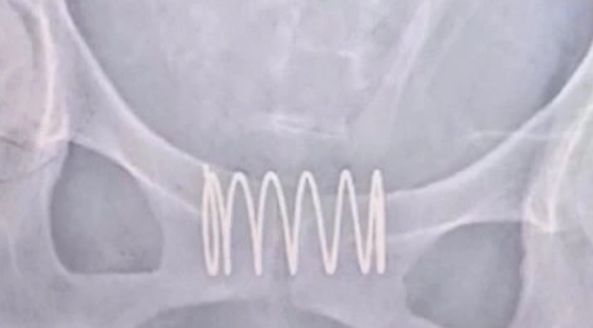

从X光片我们可以看到

这位患者体内的弹簧长约5厘米

宽度在3厘米左右